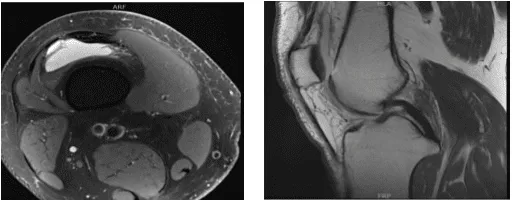

The patient, a 55-year-old man, complained of pain on the inside of his right knee when he was examined by me at my clinic. He did not respond to conventional therapy. An MRI we obtained revealed a medial meniscus tear with potential root involvement.

MRI-3T right knee non-contrast